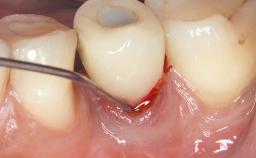

A 70-year-old female patient was referred by her general dentist to the periodontist for assessment and management of an infection associated with implant 36. The general dentist had noted suppuration on probing during examination.